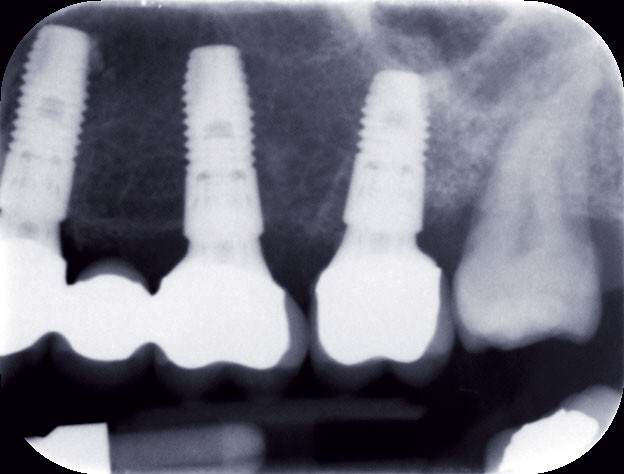

Le bridge 24-26 céramométallique et la couronne unitaire sur 27 sont réalisés. Les piliers CFAO sont transvissés sur les implants, puis les éléments céramo-métalliques sont posés. Le résultat montre un parfait respect du projet prothétique en fonction de la courbe occlusale obtenue avec le bridge transitoire réalisé avec le ProtempTM 4 et une adaptation parfaite.